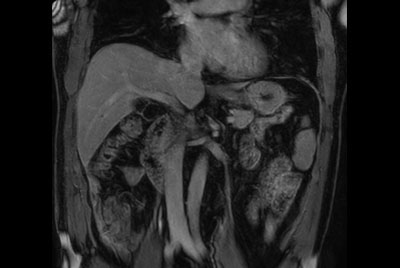

Abdomen large FOV imaging

Total Torso with SmartShim

Total Torso overview

Total torso and liver

Total Torso imaging - High dS SENSE acceleration

Total Torso imaging - MultiVane XD

Total Torso imaging